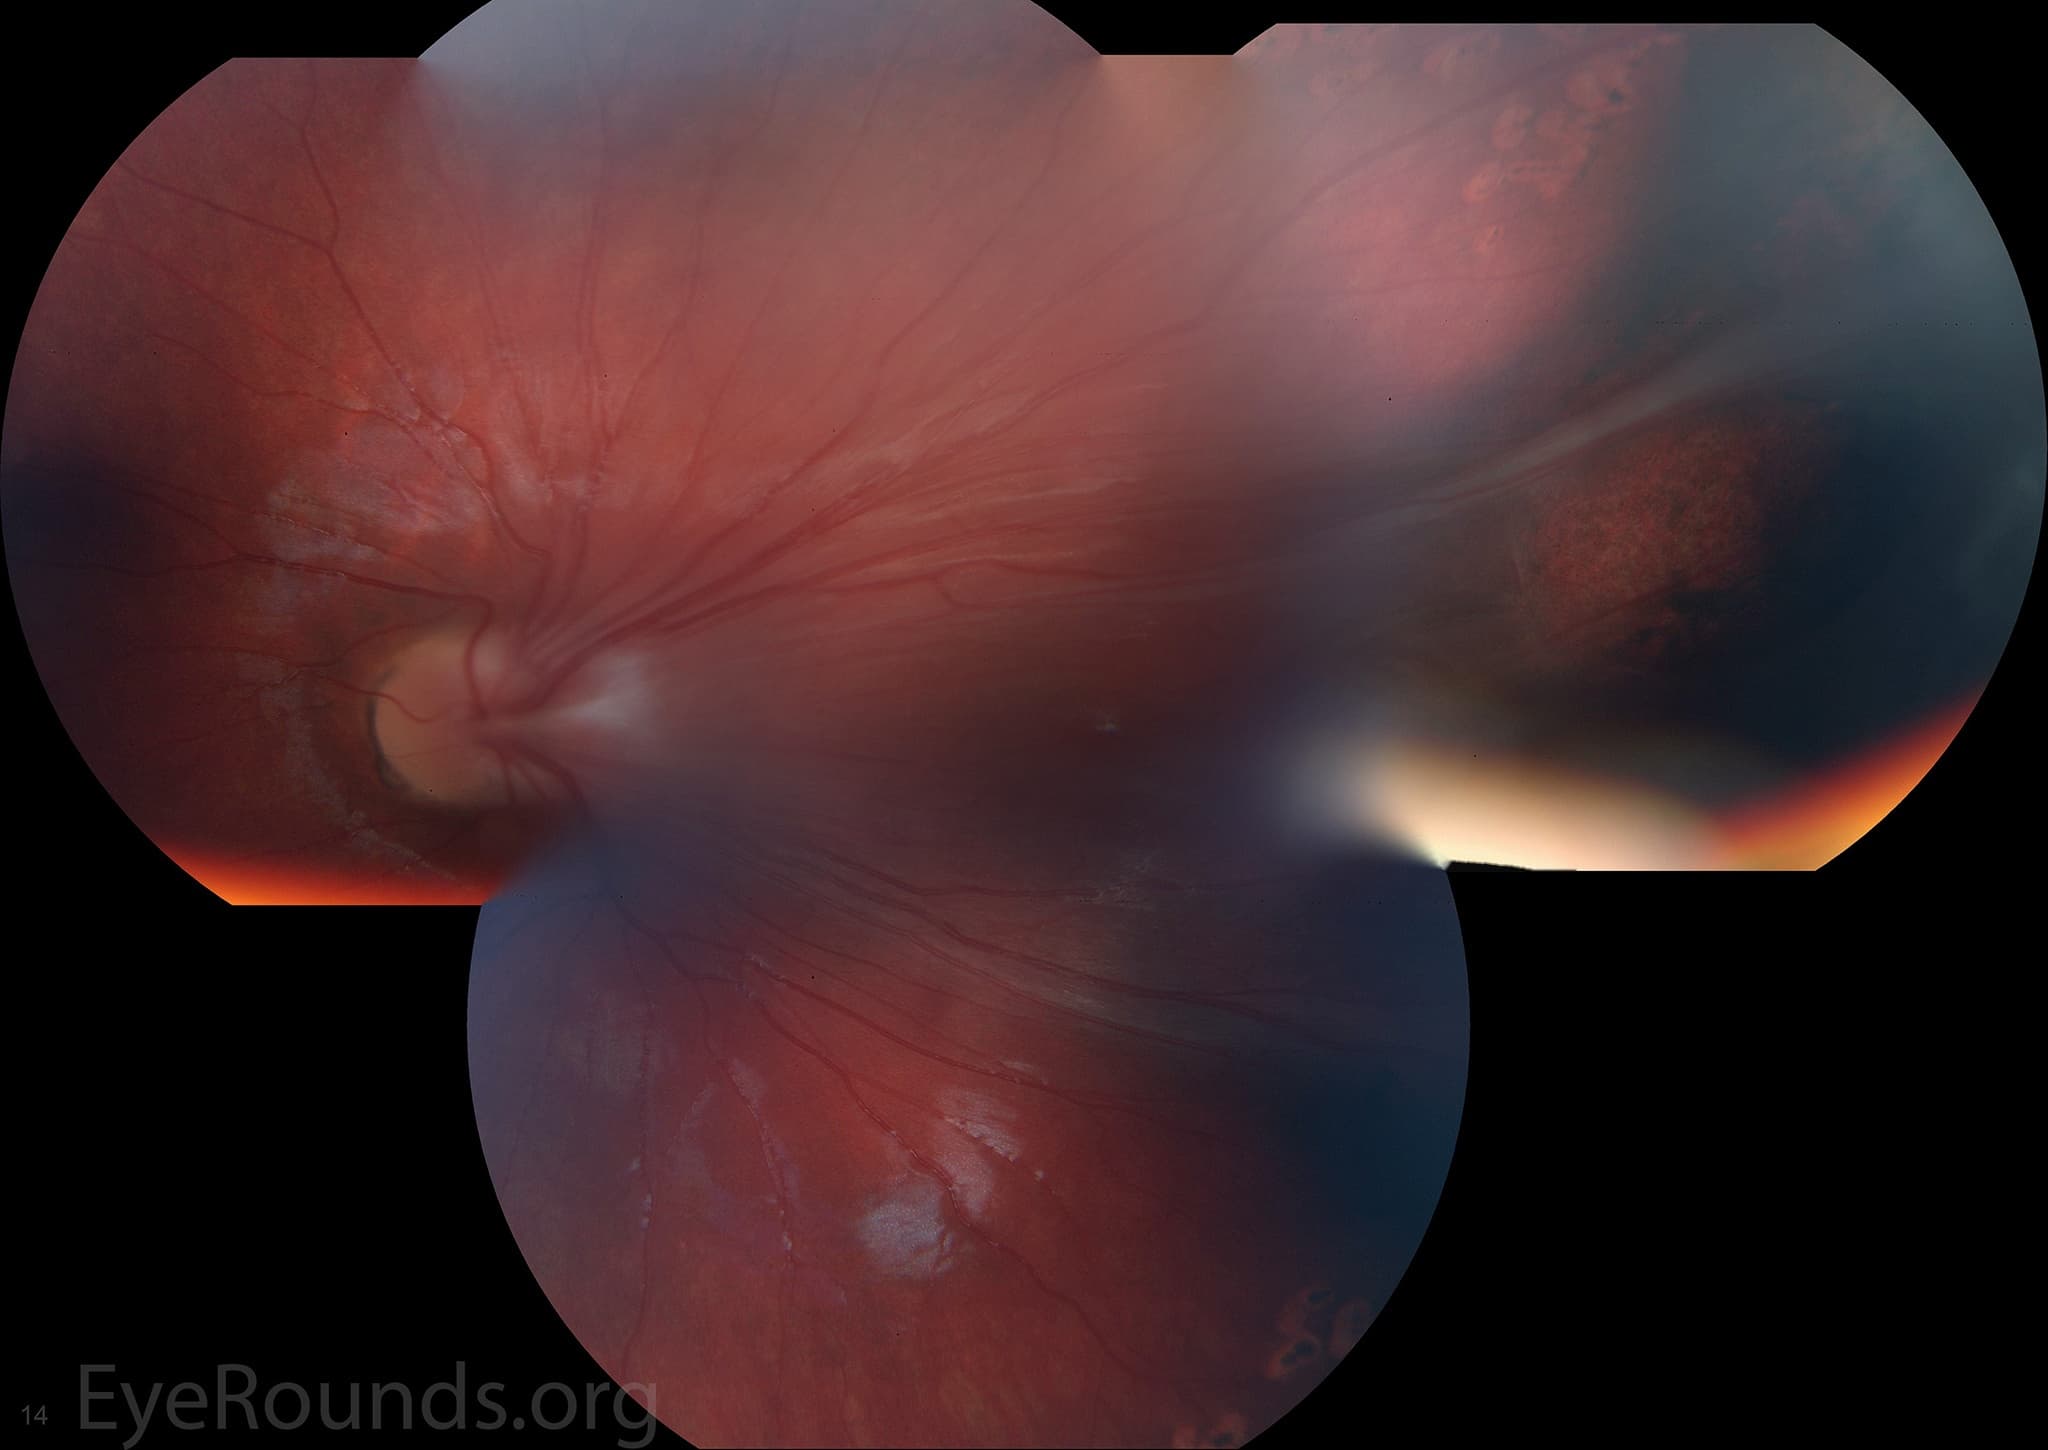

Clinical Images

High-resolution clinical photographs showing various presentations of retinitis pigmentosa (rp).